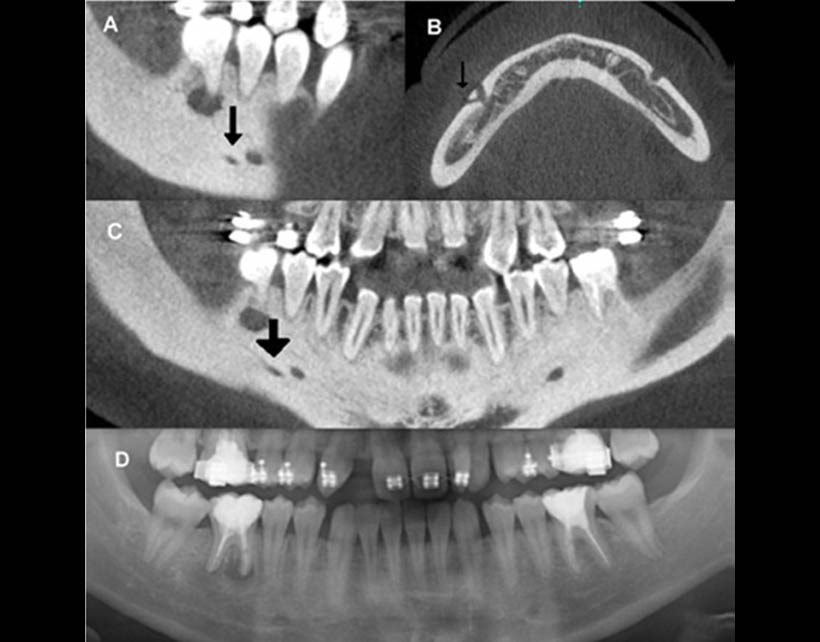

Fig. 3. La comparación entre las imágenes de TC de haz cónico (A, B, C), y la radiografía panorámica (D) de la mandíbula de un mismo paciente. La vista sagital (A), axial (B) y las reconstrucciones para-panorámica revelaron una rama accesoria posterior del nervio mentoniano emergentes a través de un agujero accesorio mentoniano. Nótese que sólo el agujero mentoniano se visualiza con la radiografía panorámica (D).